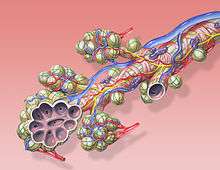

Diagram of the alveoli with both cross-section and external view. | |

The pulmonary veins play an essential role in respiration, by receiving blood that has been oxygenated in the alveoli and returning it to the left atrium.